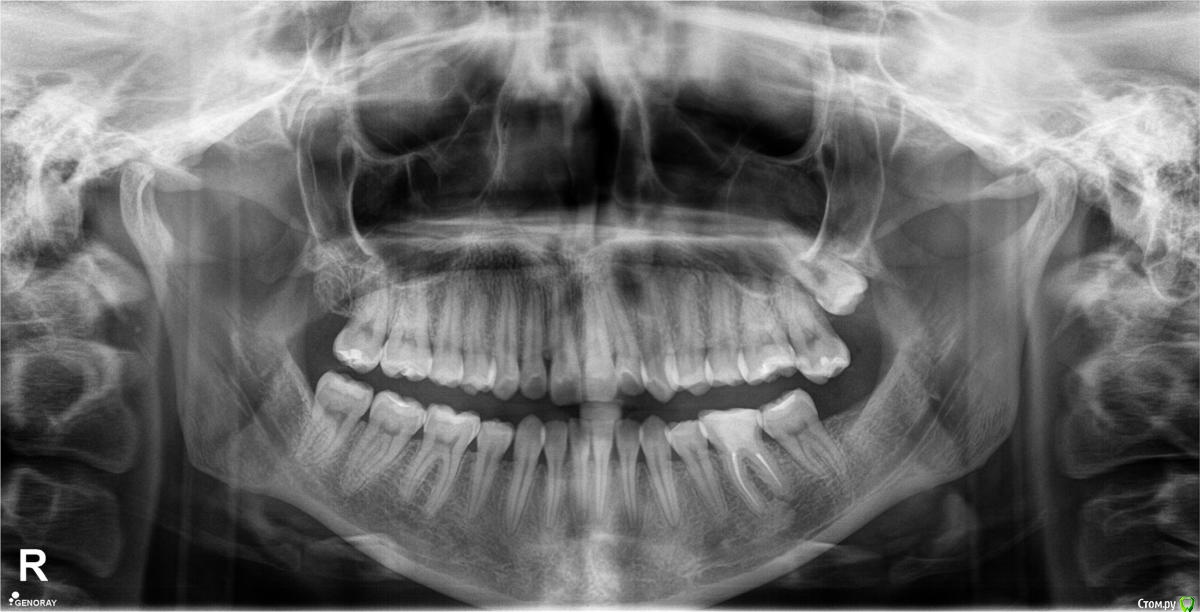

tineola Опубликовано 11 марта, 2017 Поделиться Опубликовано 11 марта, 2017 (изменено) Уважаемые врачи, здравствуйте! Мне 31 год, пол женский. Хронология:1. Ноябрь 2015 г. - септопластика и удаление кисты в левой гайморовой пазухе.2. Июль 2016 г. - со стороны этой же пазухи пролечены каналы 6-ки, через неск. дней удалена соседняя 7-ка (опустился почти до десны, беспокоил, ортодонты сошлись во мнении, что надо удалять).Через неделю появились незначительные боли в 6-ке, возникающие безотносительно нагрузки на зуб и еду. На прицельном рентгене корни 6-ки и лунка от 7го зуба были в порядке. Стоматолог уверял, что боль вызвана заживлением лунки от удаленного зуба и много других версий. Поэтому я ждала улучшений и терпела все это время.3. В последние недели боль усилилась: возникает при поворотах, наклонах головы, появились головные боли, головокружения, заложенность в носу. Сделала КТ конкретной области беспокоящего зуба, на которой видно новообразование в левой гайморовой пазухе, как бы лежащее на корнях беспокоящей 6-ки. Стоматологи предполагают, что киста от зуба мудрости (т.е. одонтогенная), возможно, рецидив первой. К посту прикрепила:1. ОПТГ (сделана до лечения 6-ки и удаления 7-ки, но после септопластики и удаления кисты).2. Фото из свежей КТ зубов с разных ракурсов, где хорошо видно новую кисту; ссылка на Яндекс-диск с архивом этого КТ (около 350 Мб) - https://yadi.sk/d/9omJkw6x3Efc6u3. Фото одной из проекций из старой КТ ОНП до септопластики, так выглядела старая киста. 4. К сожалению, результатов гистологии первой кисты у меня нет. В центре, где меня оперировали заключение не отдали, только сказали на словах, что все в результатах нормально. Попробую на руки получить...Очень интересует ваше мнение об увиденном на снимках.Правильно я понимаю: киста от зуба мудрости? удалять надо в ЧЛХ зуб с кистой вместе? Не пострадали ли от долгого ожидания решения проблемы корни 6-го зуба? Заранее большое спасибо за помощь! Изменено 11 марта, 2017 пользователем tineola Ссылка на комментарий

tineola Опубликовано 13 марта, 2017 Автор Поделиться Опубликовано 13 марта, 2017 (изменено) Это ретенционная киста, я сомневаюсь, что она связана с зубом ...Спасибо за ответ! Сегодня удалось попасть к челюстно-лицевому хирургу.Изучили КТ, ОПТГ.Диагноз: Хронический одонтогенный верхнечелюстной синусит слева от 26 зуба. Хронический периодонтит 26 зуба. Киста верхнечелюстной пазухи слева. Ретенция и дистопия 28 зуба. (также на словах рассказал врач и на снимках показал очаги разряжения на небном корне 26го зуба). Предлагают: плановое хирургическое лечение: эндоскопическая гайморотомия слева, цистэктомия, РВК 26 зуба (как я поняла, ретроградное пломбирование с использованием МТА), удаление 28. Уважаемые врачи, прокомментируйте, пожалуйста, диагноз и план лечения. Насколько реально спасти 26й путем РВК? Огорчает еще, что большая часть пунктов хирургического лечения не проходит по ОМС Заранее спасибо! Изменено 13 марта, 2017 пользователем tineola Ссылка на комментарий

Bier Опубликовано 14 марта, 2017 Поделиться Опубликовано 14 марта, 2017 чтобы говорить о необходимости РВК - надо видеть нормальный снимок 26 зуба. Он не попадает в срез КТ на вашем скриншоте.Я бы ограничился удалением 28 зуба.С 26 - нужны доп снимки. 1 Ссылка на комментарий

tineola Опубликовано 15 марта, 2017 Автор Поделиться Опубликовано 15 марта, 2017 (изменено) Сделала несколько скриншотов, прикрепляю к сообщению. Надеюсь, это то, что нужно.Может у кого-то из врачей будет время и возможность посмотреть КТ (ссылка в первом сообщении поста). Получила результаты гистологии первой кисты пазухи, которая год назад была удалена:Микроописание: Присланный материал представлен фрагментом полипозно-отечной слизистой оболочки, с концевым отделами слизисто-серозных желез. Эпителий слущен, гиалиоз базальных мембран, строма резко отечна, с диффузной лимфоцитарно-лейкоцитарной инфильтрацией. Патзаключение: хронический воспалительный процесс. Изменено 15 марта, 2017 пользователем tineola Ссылка на комментарий

ПалСаныч Опубликовано 16 марта, 2017 Поделиться Опубликовано 16 марта, 2017 Выскажу свое личное мнение: киста в пазухе не от зуба. Обычная риногенная киста, которую должен лечить лор врач. РВК не спасет 26 зуб. А только угробит. Он вообще не при делах. 1 Ссылка на комментарий

tineola Опубликовано 16 марта, 2017 Автор Поделиться Опубликовано 16 марта, 2017 Выскажу свое личное мнение: киста в пазухе не от зуба. Обычная риногенная киста, которую должен лечить лор врач. РВК не спасет 26 зуб. А только угробит. Он вообще не при делах.Большое спасибо за ваше мнение. Не хотелось бы потерять зуб и делать не имеющие смысла хирургические операции. Скажите, есть ли на снимках вообще проблемы с 26м зубом, которые мне были озвучены (разряжение ткани в районе небного корня, периодонтит)? В чем тогда может быть причина болевых ощущение в 26м зубе? Ссылка на комментарий